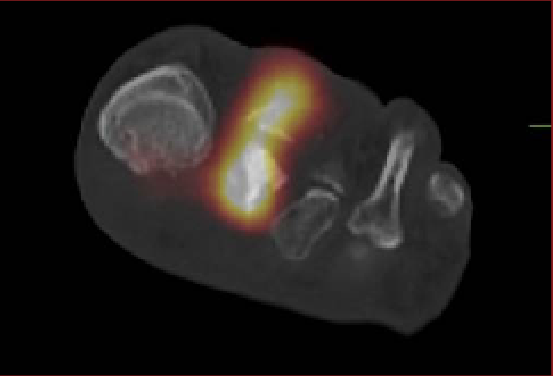

Case Study: When SPECT-CT Can Help Direct Antibiotic Therapy

This case represents an example in how this hybrid technique may be useful monitoring response to therapy. A 46-year-old male with diabetes presented to our clinic with the diagnosis of diabetic foot osteomyelitis.

He had refused surgery since the time of presentation. An infectious disease physician was involved to evaluate the patient for a long-term antibiotic regimen.

Initial Tc-99m WBC SPECT/CT demonstrated osteomyelitis of the second metatarsal head with additional involvement of the second proximal phalanx. Sequential SPECT/CT scans at two-month clinical intervals showed improvement of osteomyelitis followed by the resolution of infection after prolonged antibiotic therapy. This allowed physicians to determine when it was the proper time to stop antibiotic therapy.